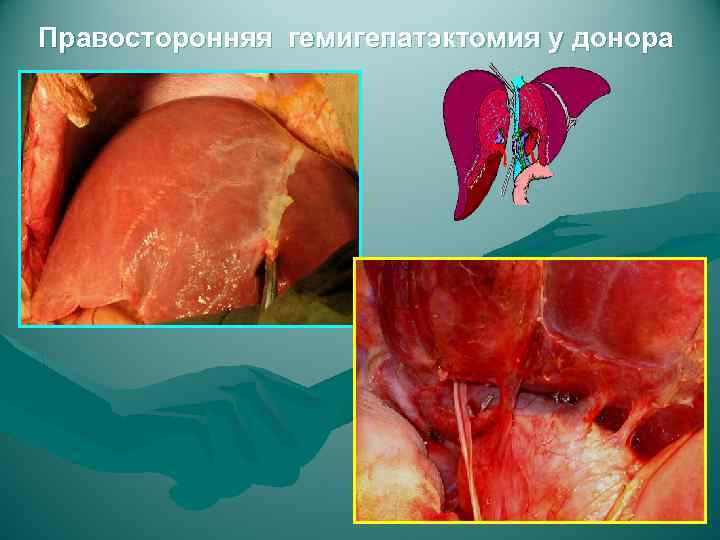

Правосторонняя гемигепатэктомия у донора

Правосторонняя гемигепатэктомия у донора

Правосторонняя гемигепатэктомия у донора

Правосторонняя гемигепатэктомия у донора